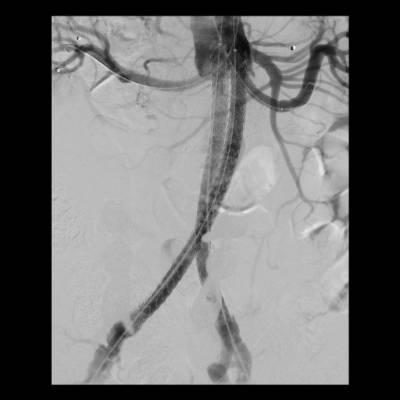

Como ejemplos de este tipo de tratamientos, "en los últimos cinco años se han implantado en el hospital seis endoprótesis ramificadas o fenestradas en pacientes con aneurismas yuxtarrenales o tóraco-abdominales. Además, el Hospital Rey Juan Carlos también realiza la técnica EVAS (Endovascular Aneurysm Sealing) para el sellado de aneurismas abdominales", explica el doctor Tomás Bolivar Gómez

, jefe asociado del Servicio de Angiología y Cirugía Vascular del Hospital Universitario Rey Juan Carlos.

El desarrollo de nuevas técnicas quirúrgicas, prótesis vasculares de última generación, y el abordaje multidisciplinar de estas patologías en colaboración con otros servicios como Cirugía Cardiaca, Cardiología, Radiología Intervencionista, Anestesiología y Medicina Intensiva permite realizar un tratamiento eficaz a un mayor número de pacientes. "La cirugía endovascular posibilita, además, reducir las complicaciones postoperatorias y la estancia hospitalaria, permitiendo el alta habitualmente en 24-48 horas", añade el cirujano vascular.

La aorta es la arteria principal del cuerpo. Su trayecto se extiende desde el corazón a través del tórax y el abdomen y se divide, aproximadamente, a nivel del ombligo originando las arterias ilíacas que dan suministro de sangre a las piernas. Las arterias que irrigan los órganos tienen su origen en la aorta a lo largo de su recorrido.

"Los aneurismas son dilataciones o "globos" en alguna parte de la aorta y su principal problema es que pueden ir creciendo de forma progresiva debilitando la pared de la arteria hasta romperse. Del mismo modo, las disecciones, hematomas intramurales o úlceras penetrantes se originan por una debilidad de la pared de la aorta y pueden provocar su ruptura o bloquear el aporte de sangre a tejidos u órganos vitales, lo que se conoce como isquemia. Cuando estas enfermedades producen una afectación extensa de la aorta, combinando los segmentos torácico y abdominal, o comprometiendo el origen de sus ramas principales, la cirugía vascular ofrece soluciones mediante técnicas endovasculares basadas en catéteres, cirugía abierta convencional o una combinación de ambas", concluye el doctor Tomás Bolívar.